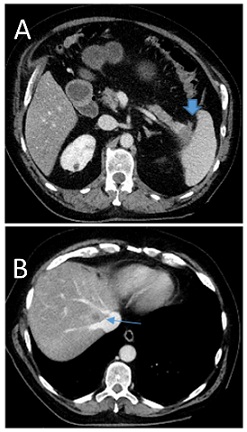

At the age of 66 the patient was diagnosed with a 4 cm pancreas tail tumor with synchronous liver metastasis in Positron-Emissions-Tomographie/Computer Tomographie (PET/CT) in 2014 (Figure 1A&1B). Initial CA 19-9 was 181 kU/l (Figure 2) in June 2014. The patient was oligosymptomatic, he had spine pain, fatigue and no significant weight loss. At the age of 65, he had some kind of belly pain and received a CT of the abdomen in 2013, however his pancreas and other organs were clean. In retrospective the cancer was already seen on that CT without liver metastasis (Figure 3). His risk factor for pancreas carcinoma were smoking, regular alcohol consumption and a positive family history for cancer. He was a smoker (30 pack-years (PY)) and quit in 1982. Despite the presence of liver metastasis the patient wished to be operated on. Preoperative the patient received pseudo-neoadjuvant chemotherapy mFOLFIRINOX (15 cycles) from May 2014 until January 2015.  After chemotherapy a regression of the tumor, liver metastasis (Figure 4) and CA 19-9 (Figure 2) was observed. However a new 19 mm metastasis of liver occurred. Despite that fact a successful pancreas tail resection with lymphadenectomy and splenectomy was performed on in April 2015. Based on the histopatology the tumor staging was pT3, G3, L0, V1, Pn1, R0. The morphology of the tumor was poorly differentiated adenosquamous carcinoma and tumor size was 2.5 cm diameter. Radiofrequency Ablation (RFA) of liver metastasis were done in April 2015. One year postoperatively diabetes mellitus type 2 was diagnosed and insulin therapy was started in March 2015.

Figure 4: Axial images from a contrast-enchanced CT scan of the abdomen after neo-adjuvant chemiotherapy in our patient with metastatic pancreas tail carcinom showing a regression of liver metastasis.